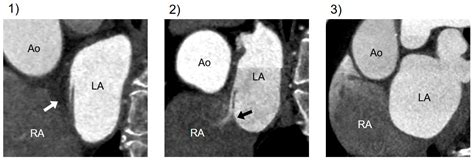

• Echocardiogram: This is a non-invasive test that uses sound waves to create images of the heart. A transesophageal echocardiogram (TEE) is often used to get a clearer view of the heart's structures.

• Bubble Study: During an echocardiogram, a saline solution with microbubbles is injected into a vein. If the bubbles appear in the left atrium, it indicates the presence of a PFO.

• CT Scan: A computed tomography scan can provide detailed images of the heart and help identify a PFO.